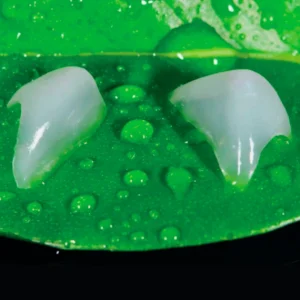

1.Two-way screw expander product features:

Expand the narrow fork to achieve bidirectional expansion